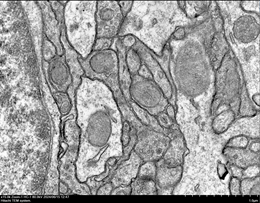

透射电镜(TEM)通过对组织细胞样本进行树脂包埋切片,60-80nm厚度的超薄切片,经过重金属铅、铀染色后于透射电子显微镜中进行几千至几万倍的放大成像,从而能够清楚的观察到在普通光学显微镜下无法看清的动植物细胞内的超微结构,比如线粒体、内质网、高尔基体、溶酶体、自噬小体、凋亡小体、叶绿体、液泡、细胞内细菌或病毒侵染等结构及病理变化。透射电镜超薄切片除了能够显示细胞内的超微结构之外,还可用于观察病原微生物,如各类细菌真菌等。目前已经广泛应用于细胞生物学、组织学、病毒学、病理学、分子生物学、材料科学等诸多研究领域,是观察和研究物质超微结构的强有力工具。